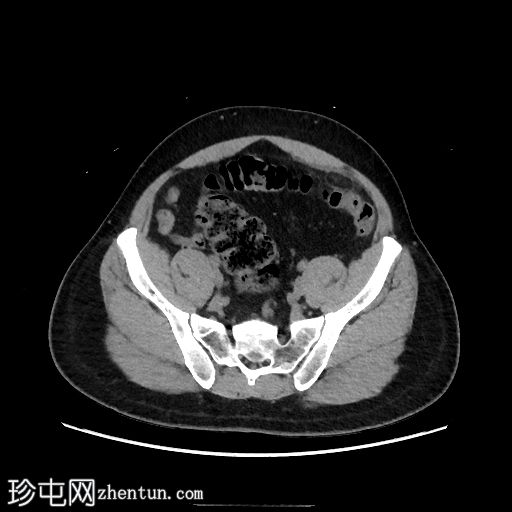

轴位增强扫描(门静脉期)

乙状结肠和远端降结肠可见轻度环周壁增厚

结肠周围可见卵圆形脂肪密度病变,周围环绕软组织密度环,并可见脂肪条索状改变,符合大网膜垂炎的典型表现

未见憩室炎证据